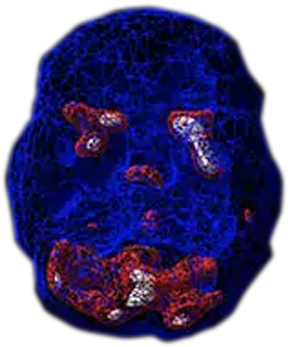

Brain imaging shows that panic disorder is not a character flaw or personal weakness. It is associated with biological changes in the brain. Brain SPECT scans show that overactivity in the basal ganglia is commonly seen in people with anxiety and panic disorder but there can also be other areas with abnormal activity.

SPECT (single photon emission computed tomography) is a nuclear medicine study that evaluates blood flow and activity in the brain. Basically, it shows three things: healthy activity, too little activity, or too much activity. A healthy “active” scan shows the most active parts of the brain with blue representing the average activity and red (or sometimes red and white) representing the most active parts of the brain. In the healthy scan on the top right, the most active area is in the cerebellum, at the back/bottom part of the brain. The brain scan below it is from a person with panic disorder and shows marked increased activity in the basal ganglia.

Panic Disorder Scan